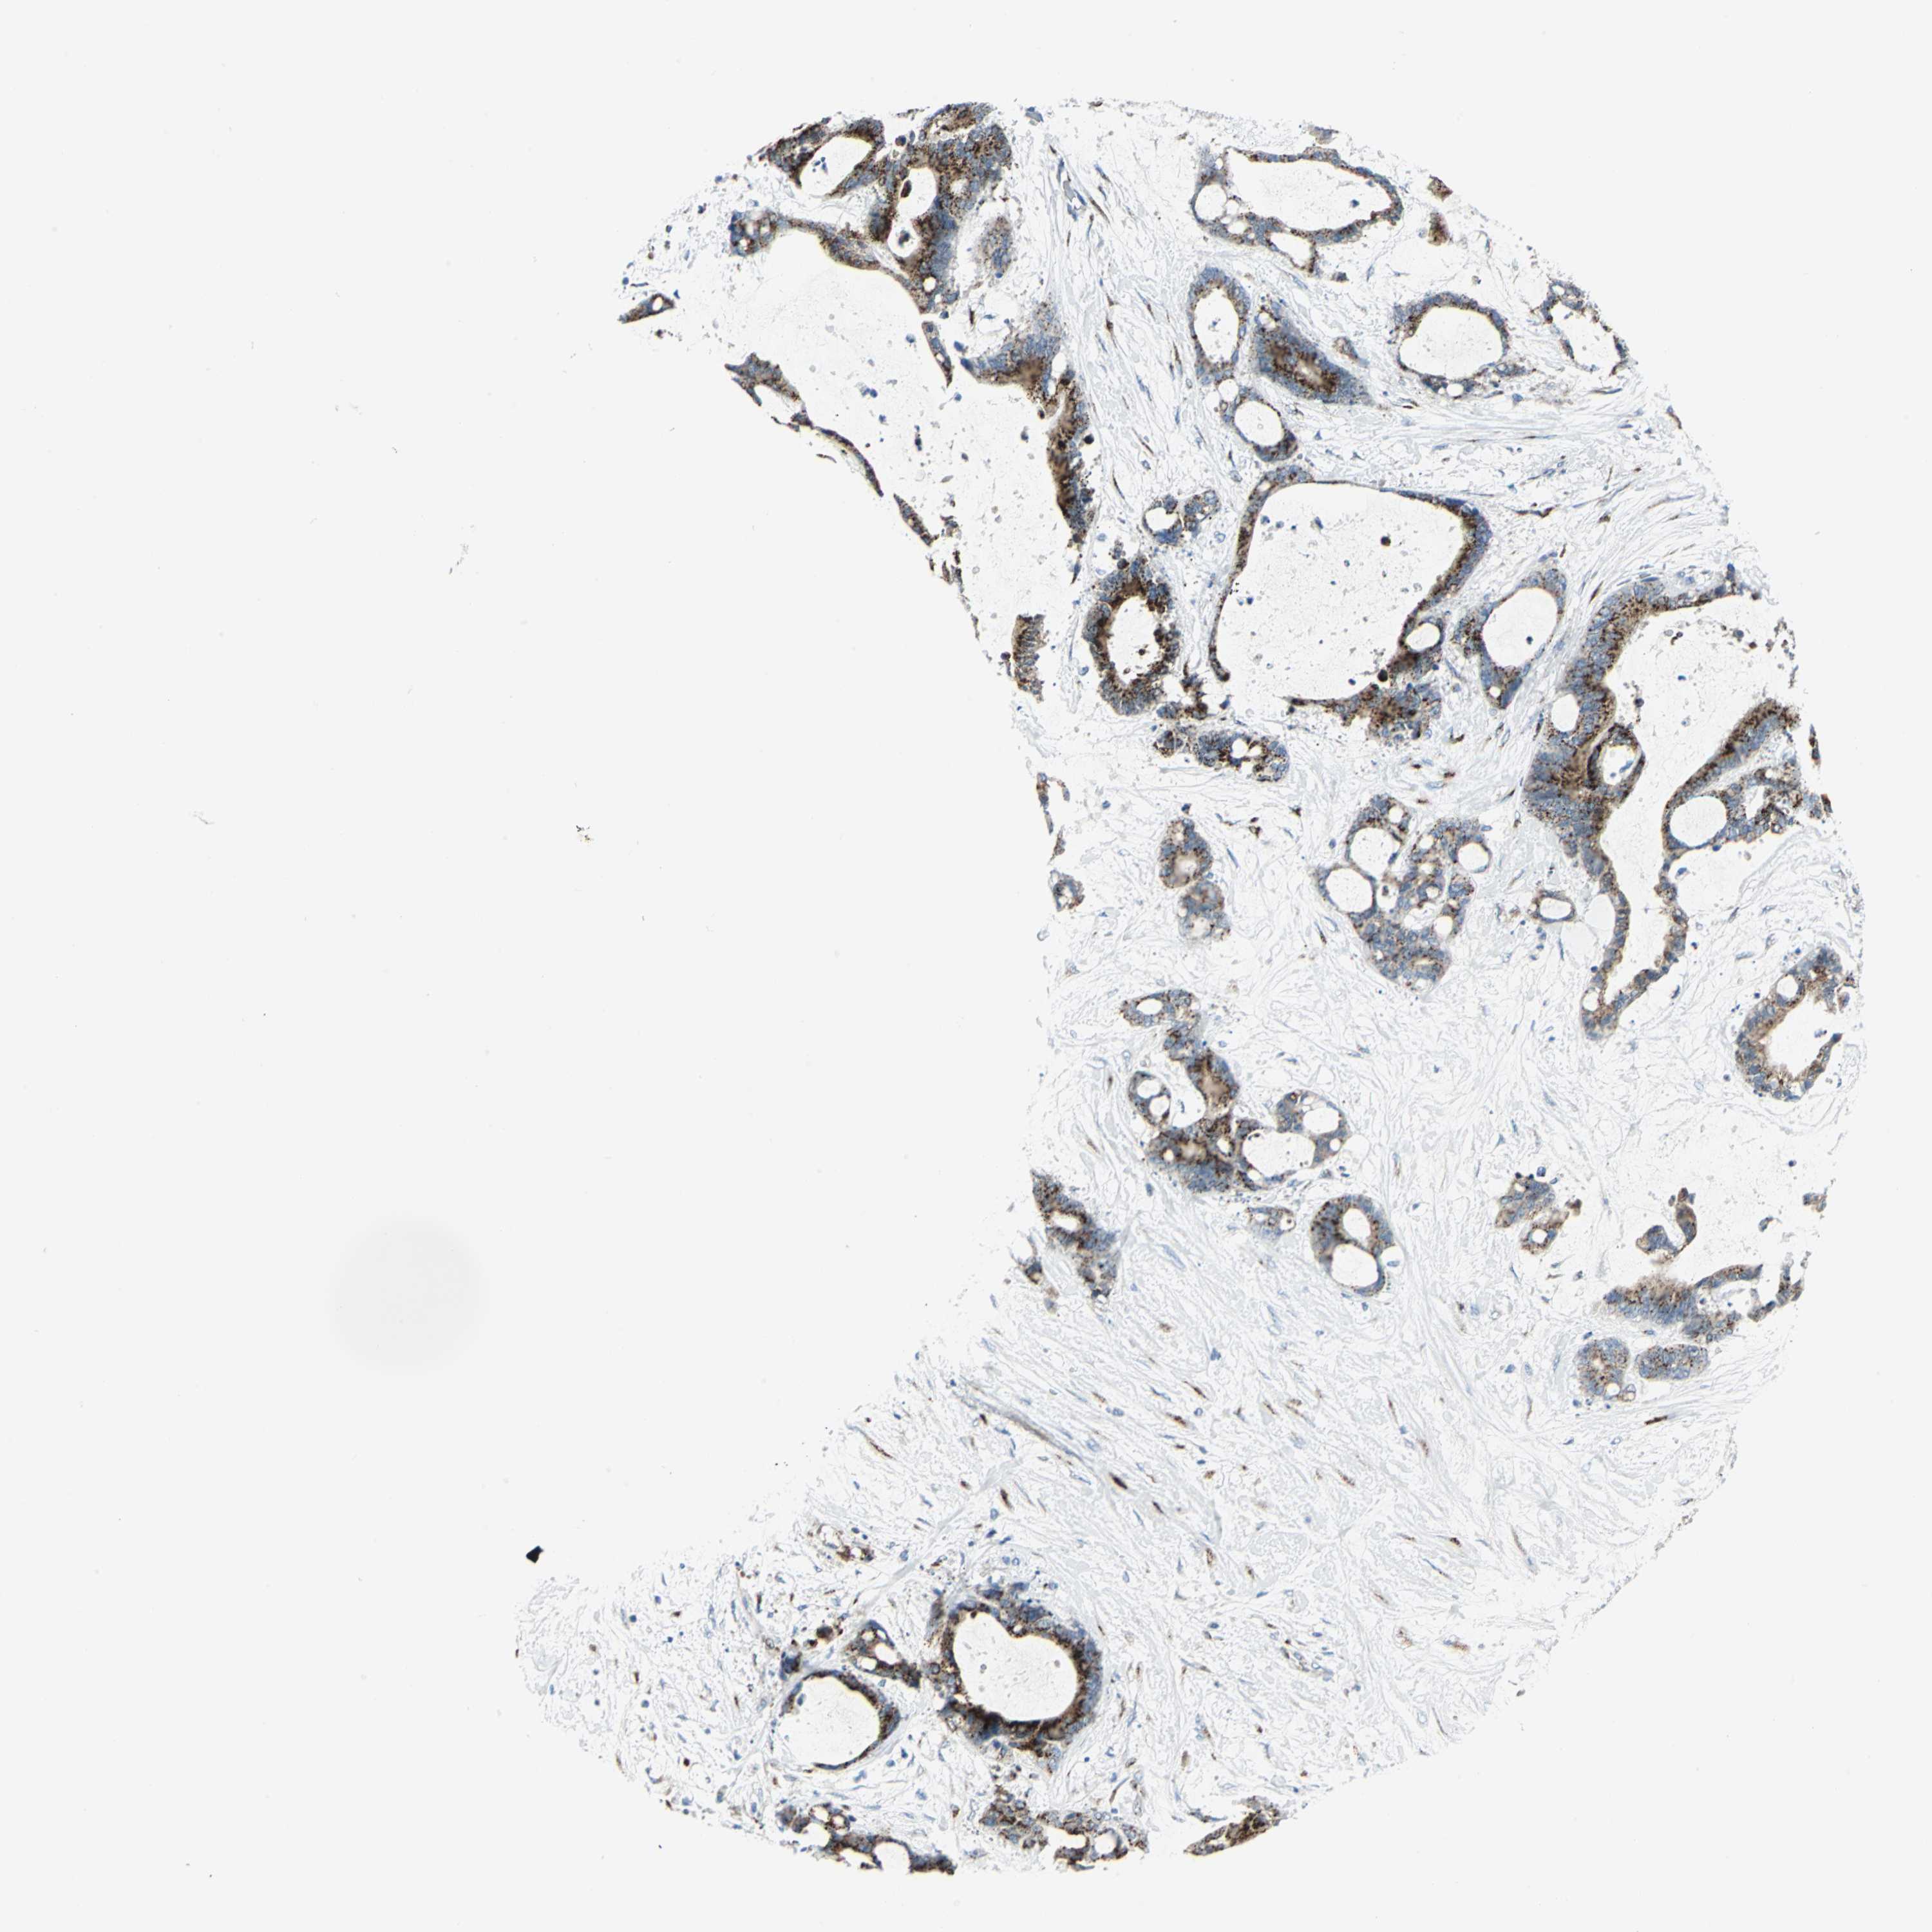

LIVER CANCER - Protein expressioni

A mouse-over function shows sample information and annotation data. Click on an image to view it in a full screen mode. Samples can be filtered based on level of antibody staining by selecting one or several of the following categories: high, medium, low and not detected. The assay and annotation is described here.

Note that samples used for immunohistochemistry by the Human Protein Atlas do not correspond to samples in the TCGA dataset.

Antibody stainingi

Antibody staining in the annotated cell types in the current human tissue is reported as not detected, low, medium, or high, based on conventional immunohistochemistry profiling in selected tissues. This score is based on the combination of the staining intensity and fraction of stained cells.

Each image is clickable and will lead to virtual microscopy that enables deeper exploration of all samples and also displays staining intensity scores, fraction scores and subcellular localization as well as patient and tissue information for each sample.

Antibody CAB006254

Staining

High

Medium

Low

Not detected

Intensity

Strong

Moderate

Weak

Negative

Quantity

>75%

75%-25%

<25%

None

Location

Nuclear

Cytoplasmic/membranous

Cytoplasmic/membranous,nuclear

Cholangiocarcinoma

Carcinoma, Hepatocellular, NOS